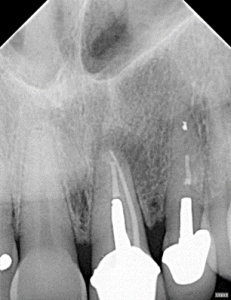

Apical Microsurgery / Apicectomy

Clinical Cases